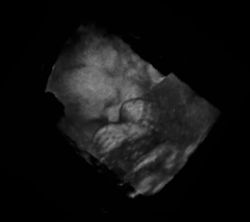

Das Ungeborene kann in der Gebärmutter nahezu komplett untersucht werden, da noch keinerlei Gasüberlagerung vorliegt und die Knochenbildung erst am Anfang steht:

- auch Lunge – Magen – Extremitätenknochen u. a.

Von den Monitorbildern werden zur Dokumentation Ausdrucke, sogenannte Sonogramme, oder gelegentlich Videoaufnahmen gemacht. Schwangeren wird häufig auch ein Bild ihres ungeborenen Kindes überlassen.